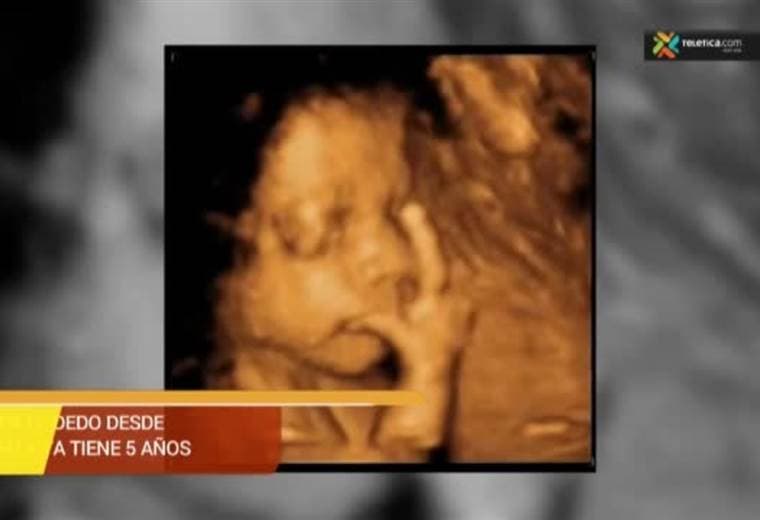

Felipe se chupa el dedo desde antes de nacer y a sus casi 5 años llevarse el dedo izquierdo a la boca es su ritual para dormir.